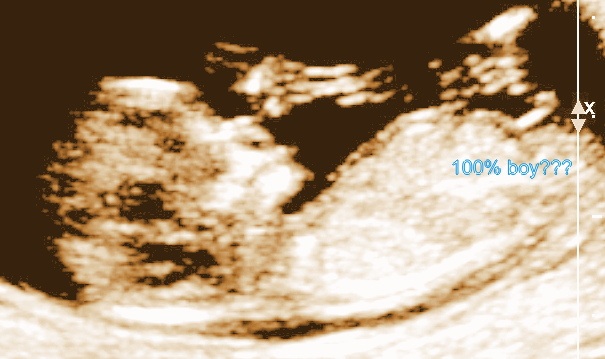

Is it definately blue for us?? :) TIAAttachment 9528

Nub aren't super accurate until 12.5 to 13 weeks but its usually a case of girl nubs could rise until then - i've not heard about one flattening out. Its never 100% anyway but theory goes angle above 30 degrees its a boy, below a girl (girl nubs are usually flat).

I'm LOLing a little at "100% boy" followed by ???

Haha yeah Inky there really isnt a question in my mind now i found this pic...perhaps it shud say 99%?? Lol we have 6x luvly boys and 1x pretty girl already so im lol'ing at boy #7!!!!! Haha ;)